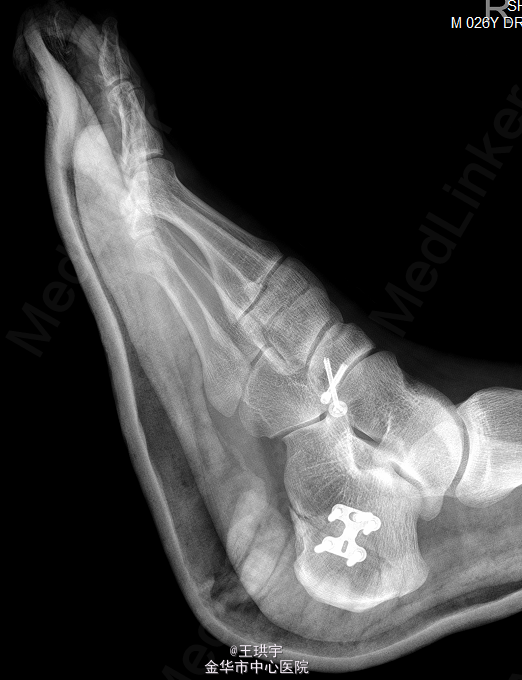

右足副舟骨畸形

后天性扁平足

患者,男,26岁,因“右足部外伤后疼7余年,加重6月 ”入院。

右踝及足背肿胀不明显,右足副舟骨可见明显红肿,皮温正常,足趾活动无殊,末梢循环感觉正常。余肢体无殊。外院 X片示副舟骨畸形.

初步诊断:右足副舟骨畸形,后天性扁平足.在全麻下行“右跟骨截骨内移+副舟骨切除+舟骨切复内固定术+石膏固定术”.